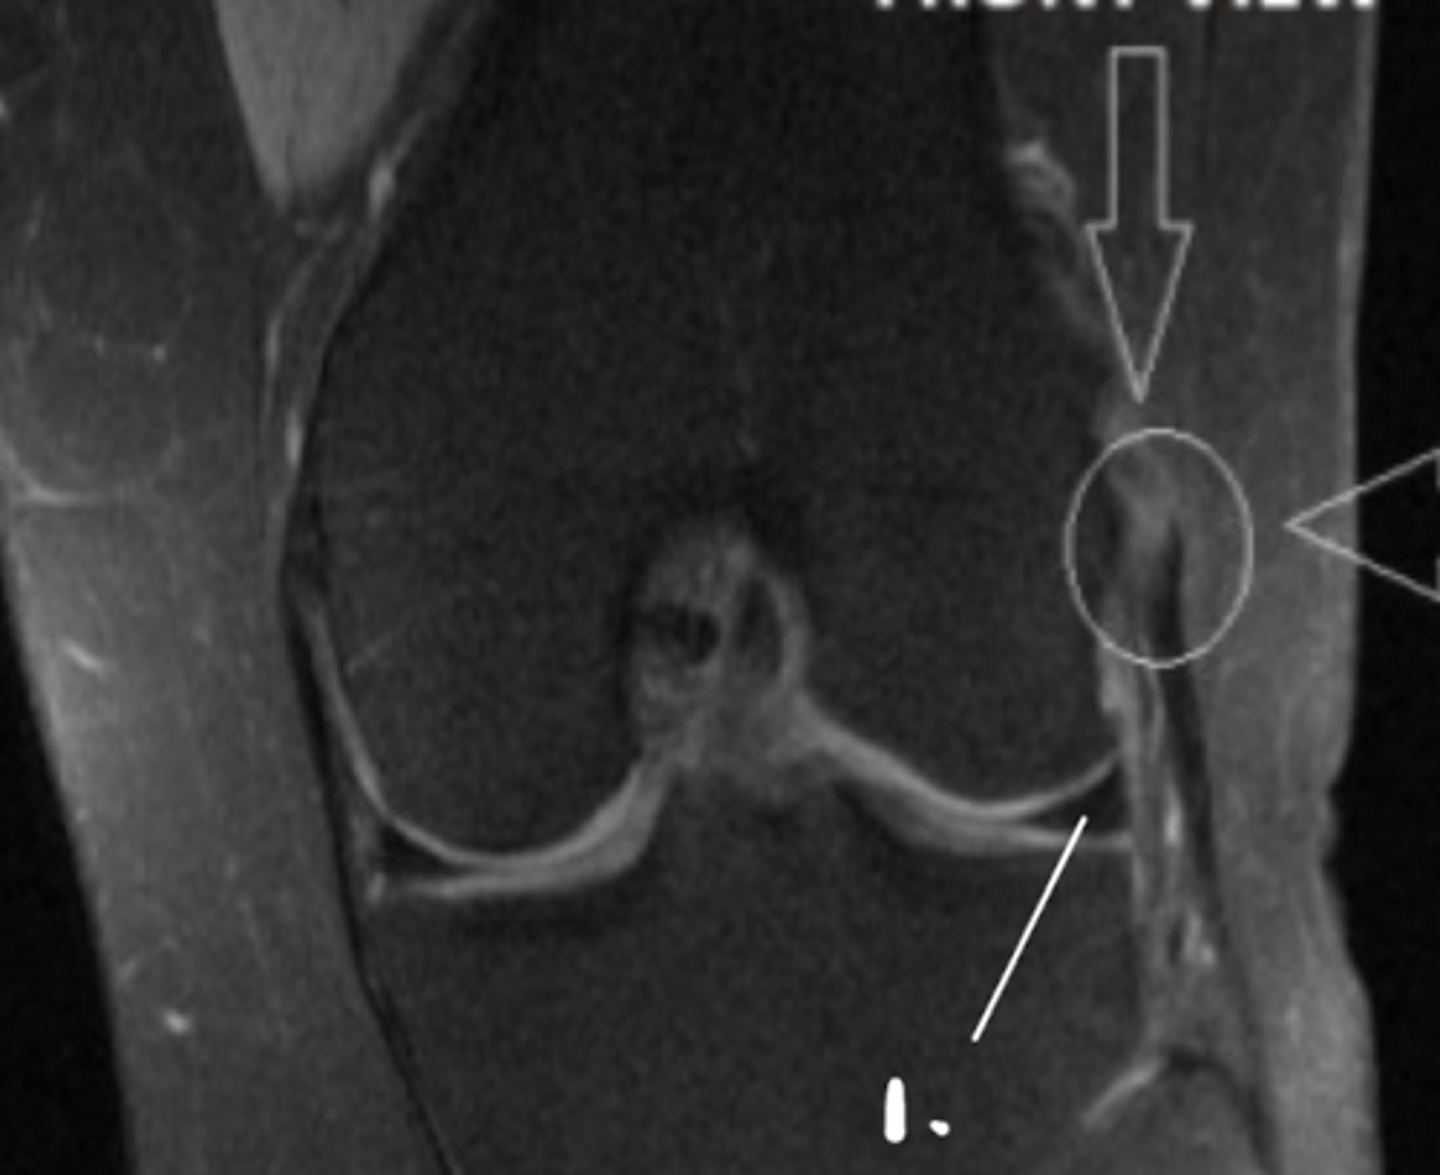

Torn LCL

Define the pathology. (#1 is just pointing to the meniscus)